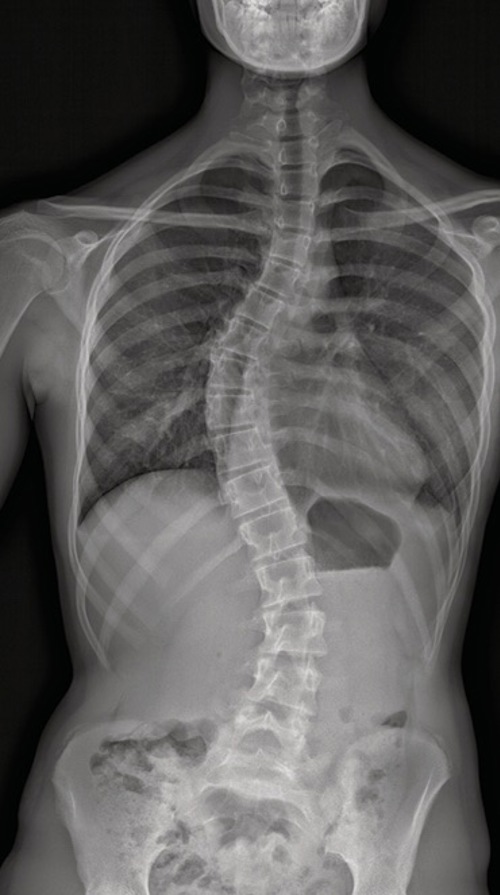

Roentgenbild2

Röntgenbild einer Skoliose.